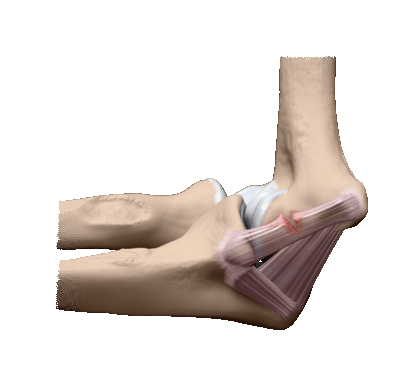

Схематичное изображение процедуры.